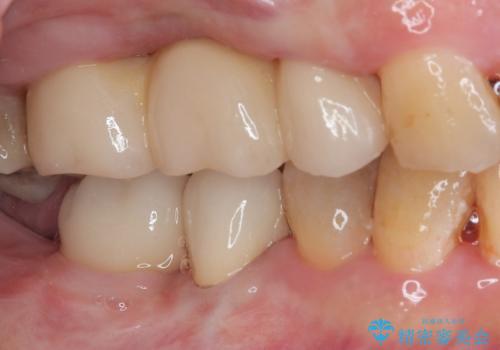

矯正治療を仕上げ、必要に応じて歯周外科処置を行い、適宜インプラントを埋入しながら咬み合わせを回復させていくこととしました。

最終的に奥歯はオールセラミッククラウンによる補綴治療を行うこととしました。

治療前は磨き残しが多く見られ、全体的に歯肉が腫れている状態でしたが、抜歯の必要な歯を抜いたことで口腔内の環境が改善され、磨き残しも少なくなってきました。

インプラントにより咬合が回復したことで、治療開始時に認められた上顎前歯の動揺も改善されました。